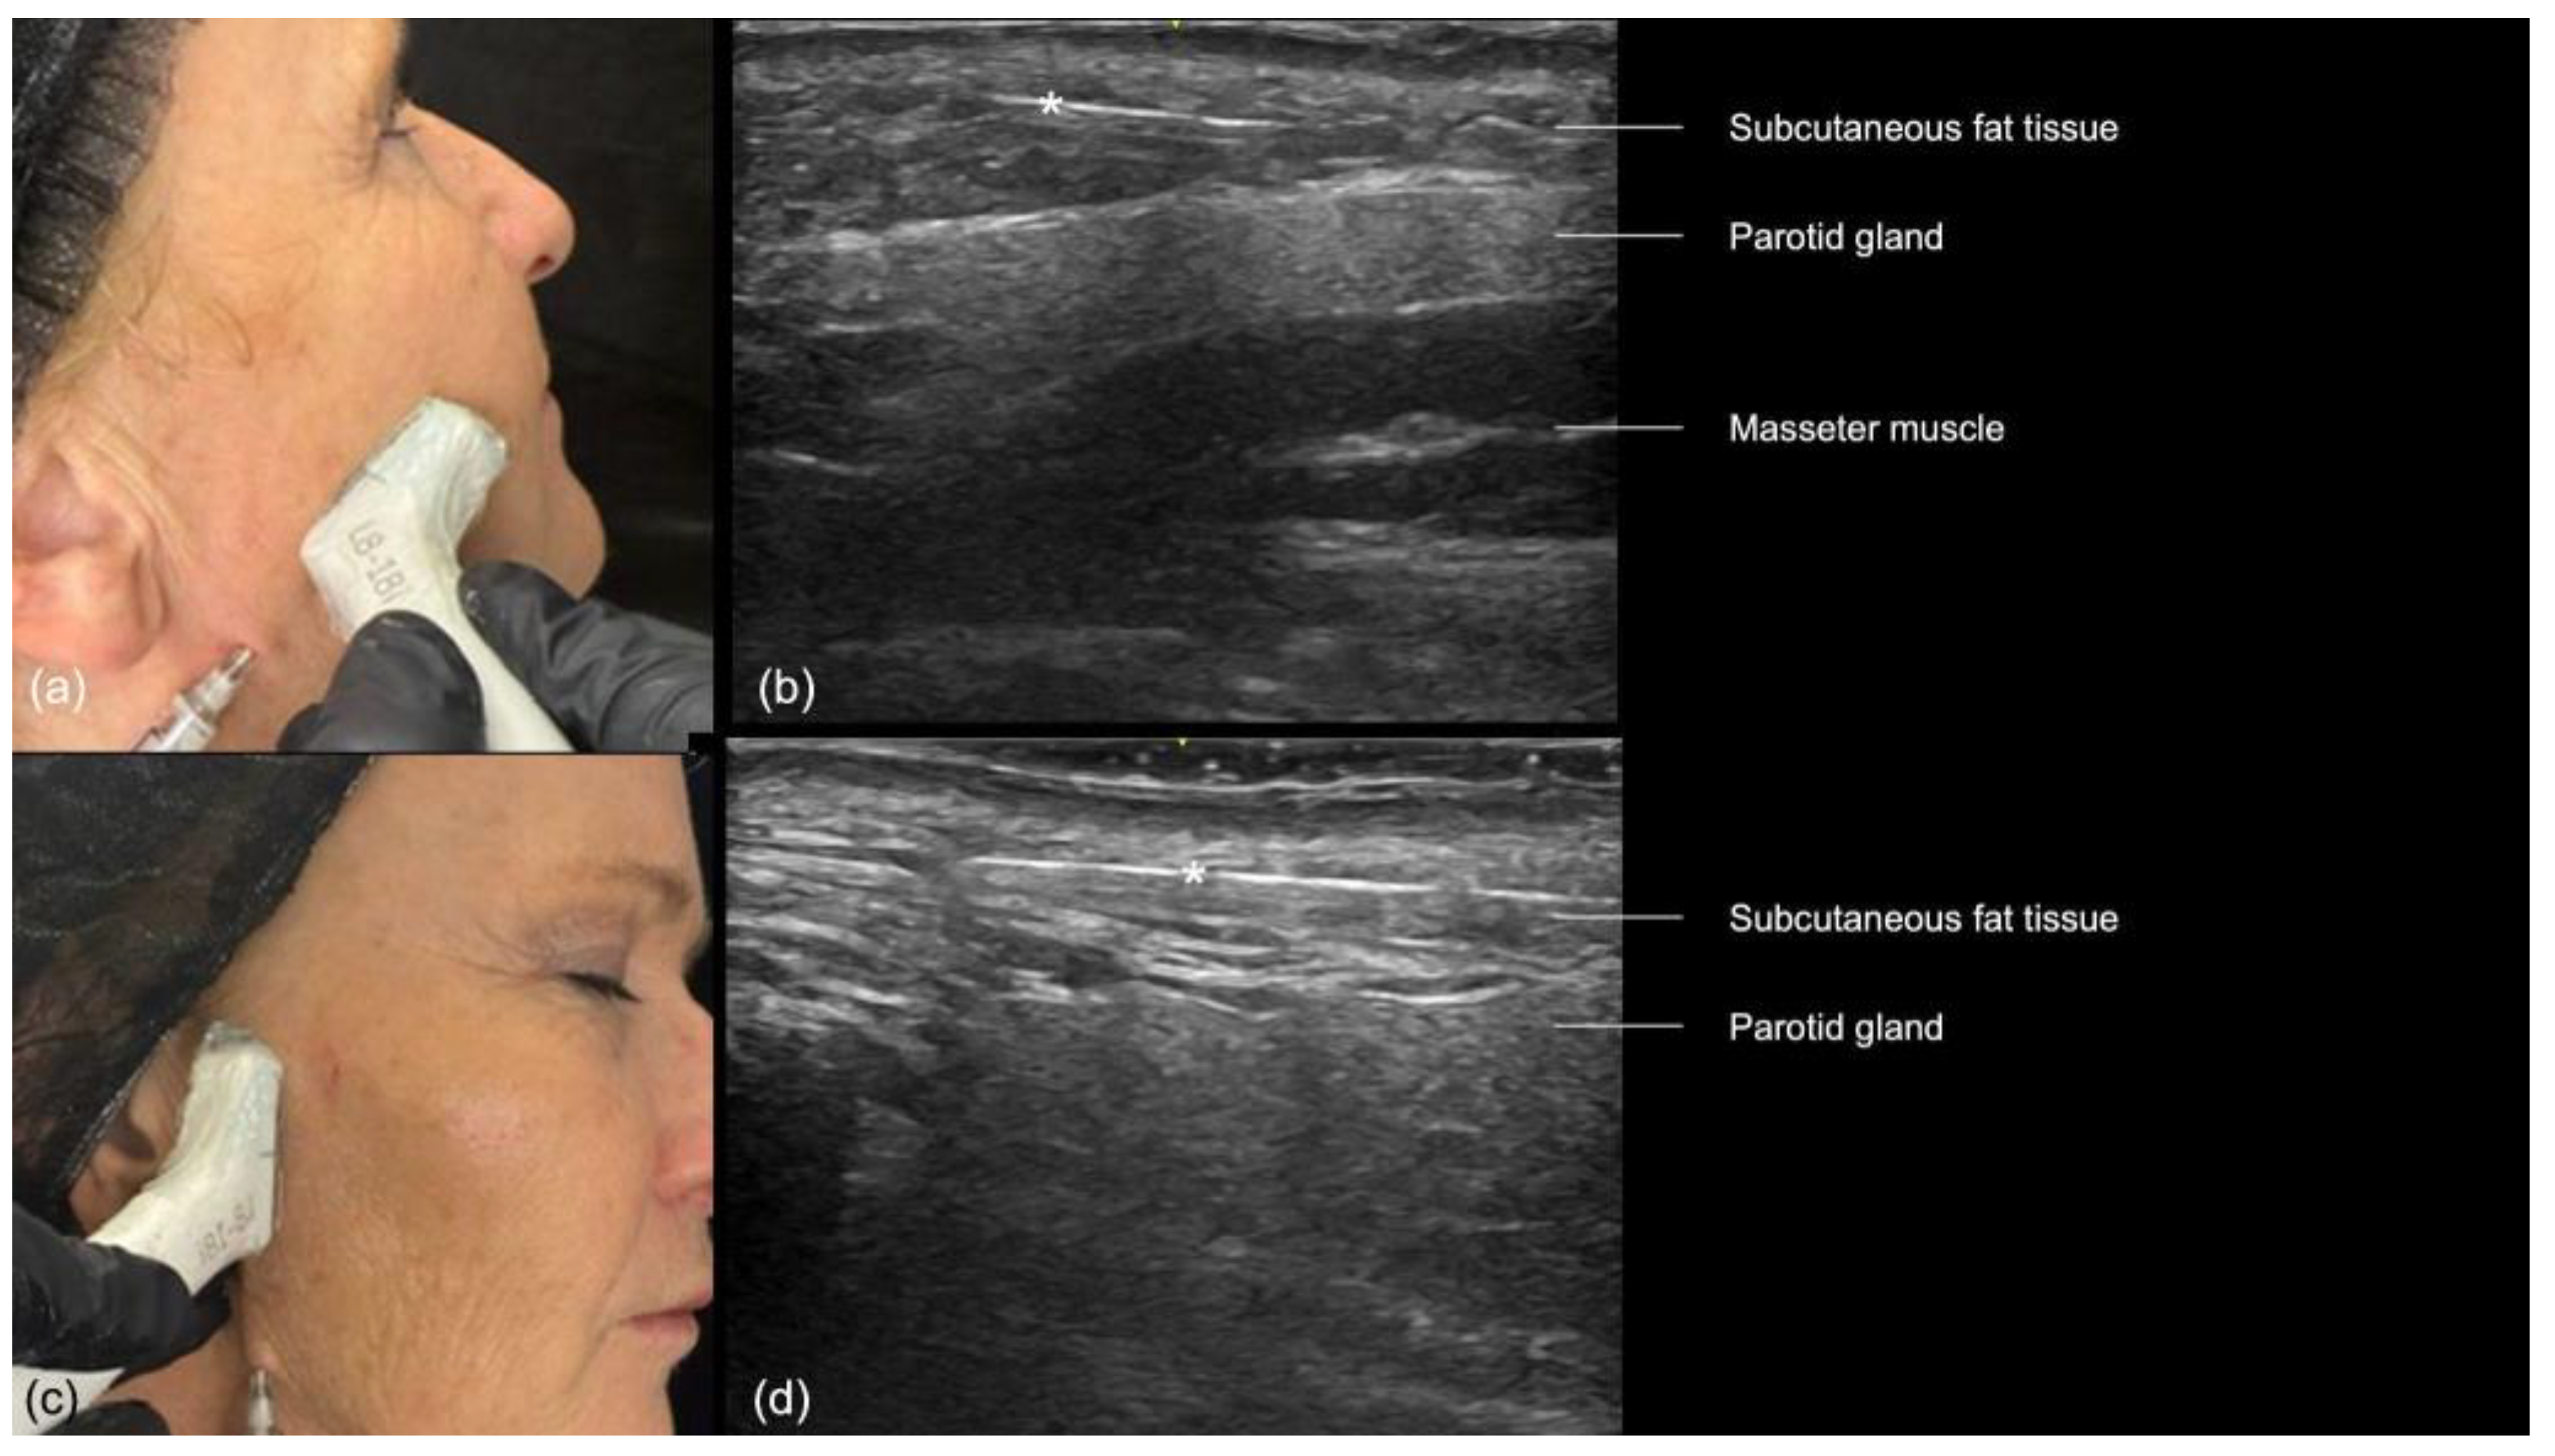

In the preauricular region, the sonographic anatomy is more complex due to the proximity of the parotid gland. The layers visible on ultrasound (Figure 12a–d) include the skin, subcutaneous fat, SMAS, transverse facial artery, parotid fascia, parotid gland, and masseter muscle [16]. The subcutaneous tissue is particularly thin in this area, often measuring between 2 and 4 mm, which increases the risk of inadvertently injecting filler into the parotid gland. This can lead to serious complications, including inflammation, abscess formation, and chronic parotitis [16]. Even if the filler is placed near the glands, there is still a chance of developing inflammation [17]. Additionally, anatomical variations such as accessory parotid glands (Figure 12d) or prominent anterior prolongations (Figure 12a) that cover the upper third of the masseter muscle should be carefully avoided to prevent these issues [16].

Figure 12.

US of the preauricular region layers. (a) Prominent anterior prolongation of the parotid gland. (b) A normal lymph node inside the parotid gland with a hyperechoic hilum (transverse panoramic and longitudinal view at 18 MHz, respectively). (c) Color Doppler highlighting the transverse facial artery emerging between the masseter muscle and the parotid gland. (d) Grayscale US demonstrating an accessory parotid gland superficial to the masseter muscle (transverse view at 18 MHz).

The “scan while injecting” technique should be used in this region, which will constantly assess the cannula’s position to ensure that it is outside the parotid gland and above the parotid masseteric fascia (Figure 16). Each time the direction of the cannula is changed, its position should be reassessed.

Figure 16.

US-guided injection in the preauricular region. (a) Transverse. (b) Longitudinal injections. (c,d) B-mode US imaging showing the cannula (*) in the superficial subcutaneous plane, superficial to the parotid gland, at 18 MHz.